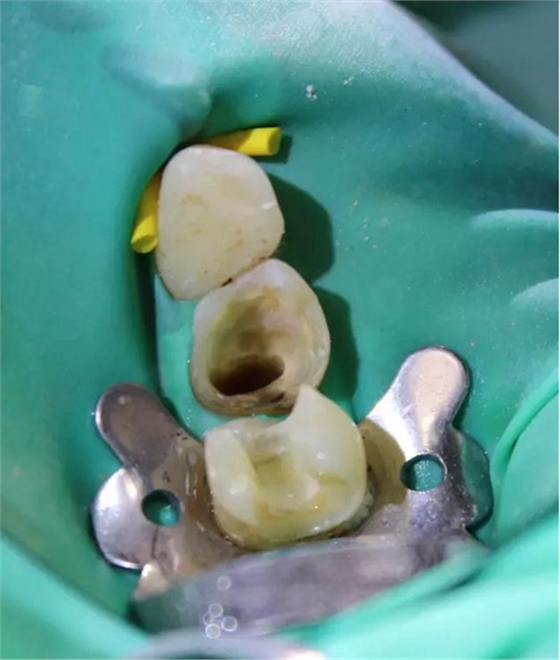

圖4 該病例中,左下4根充失敗,左下5牙髓壞死。兩個牙齒均需要根管治療和修復。

圖5 根管治療術(shù)后。左下4需要使用纖維樁,并用雙固化樹脂粘結(jié)劑粘結(jié)。左下5無需纖維樁。但2個牙齒均需要進行覆蓋牙尖的修復。